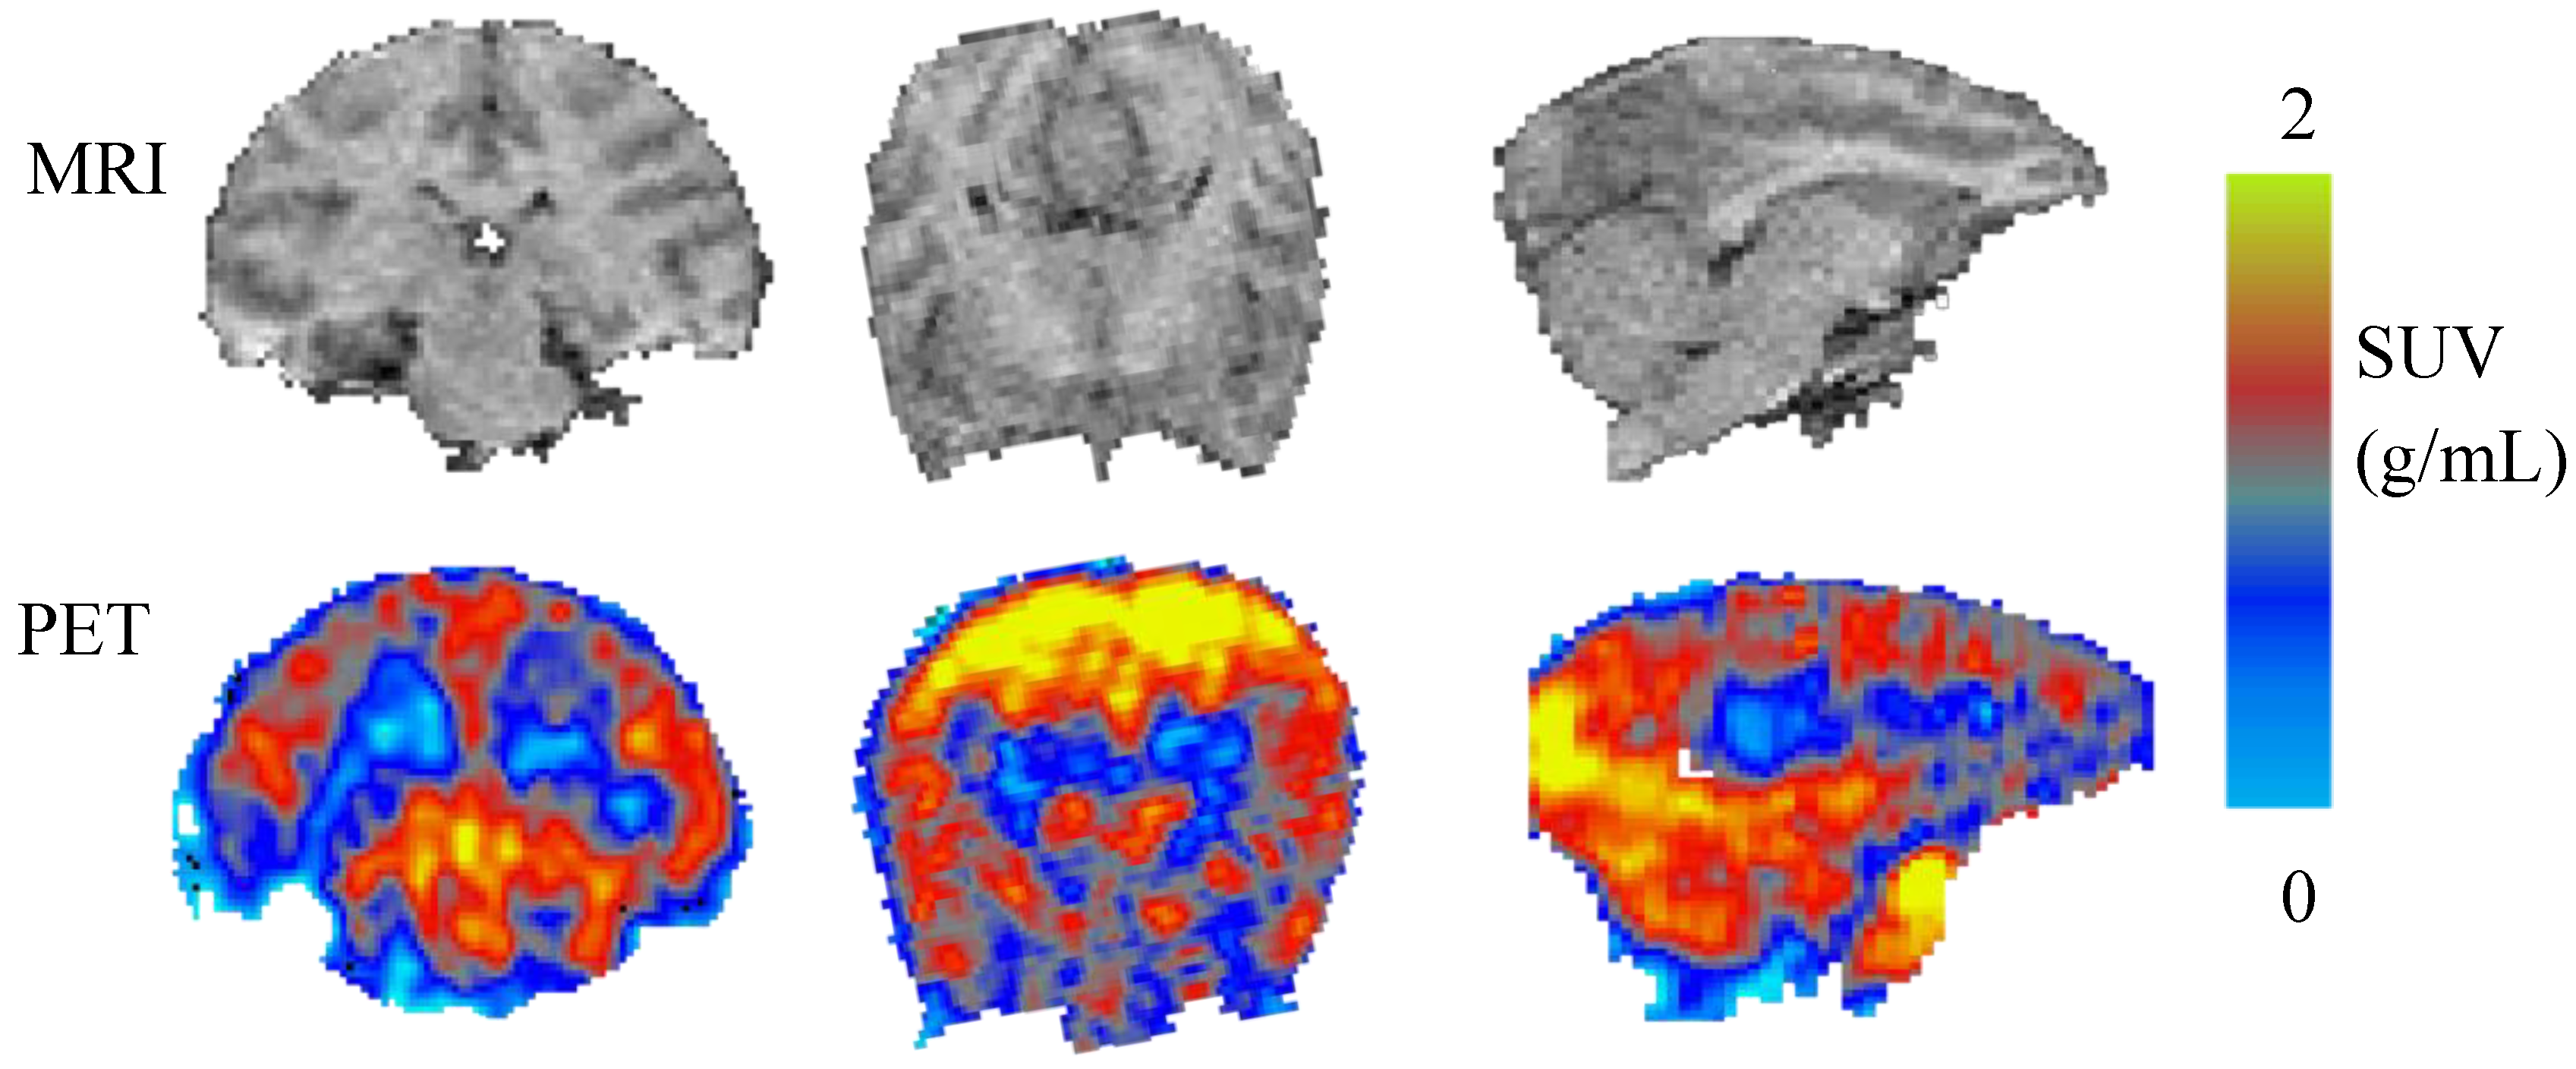

2.2. PET Imaging of [11C]Celecoxib in Baboon Brain